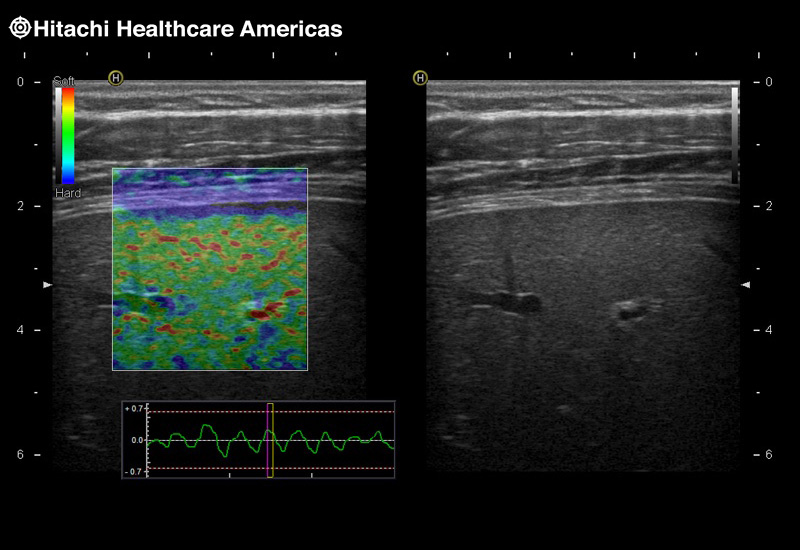

Imaging Clearly Defined

State-of-the-art digital architecture and advanced imaging features to redefine the capabilities of surgical ultrasound.

Fujifilm Healthcare’s ARIETTA Precision features state-of-the-art digital architecture and advanced imaging technologies to redefine the capabilities of surgical ultrasound.

Fujifilm Healthcare’s ARIETTA Precision features state-of-the-art digital architecture and advanced imaging technologies to redefine the capabilities of surgical ultrasound.